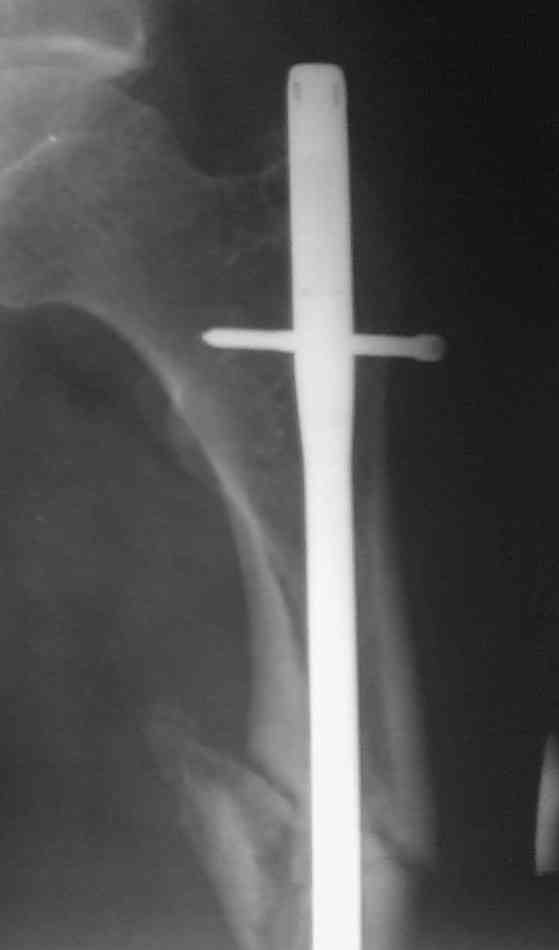

> денамизация - февраль 2006. ( 3 и 4 снимки) на сегодняшний день (снимок 5) беспокоит боли в тбс...

Учитывая точку введения - верхушка б\вертела - что бы исправить варус взял бы соответствующий гвоздь: длинную Гамму или PFN или Recon

Судя по уровню перелома, винты в шейку избыточны, подойдет и диафизарный гвоздь. Все, что нужно, это тиски и труба. Загнуть сразу ниже отверстий градусов на 8-10, и вся недолга. Последние годы у нас это рутинная практика. Предызогнутые еще с завода гвозди неудобны тем, что они уже правый-левый.

Если имеете доступ к trochanteric медуллярным штифтам TAN Smith Nephew или DePuy, где имеется offset на 8 градусов для удобства черезвертельного введения и профилактики нарушения кровеснабжения

головки (см. снимок) можно было применить штифт, в котором опороспособность достигается за счет блокирующих шурупов сверху и снизу.